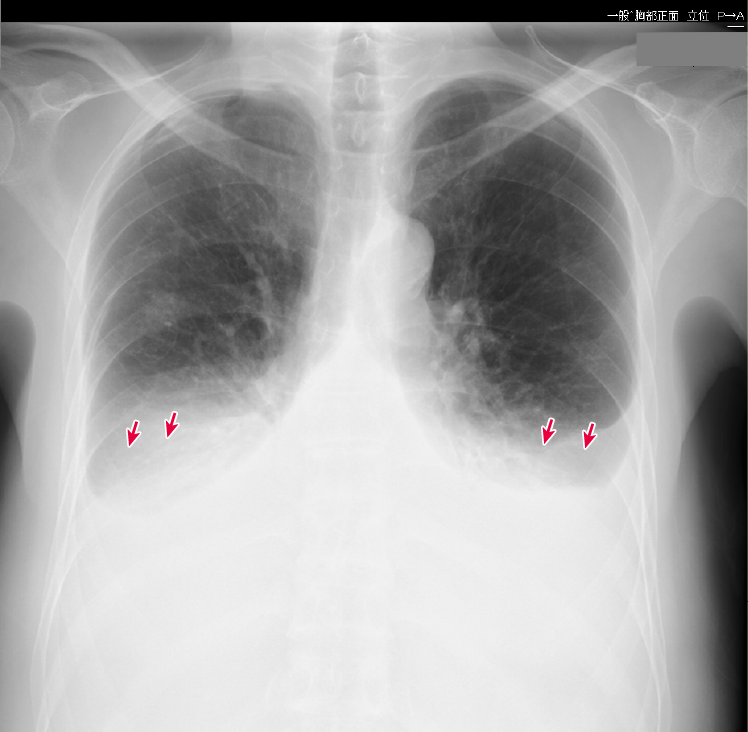

図4 症例の胸部X線画像

胸水貯留(→)